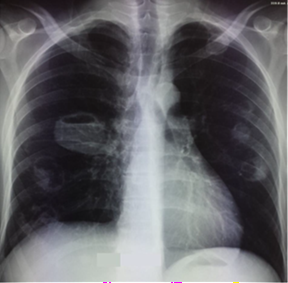

Figure1: chest

radiograph at admission shows multiple bilateral opacities in the exclave.